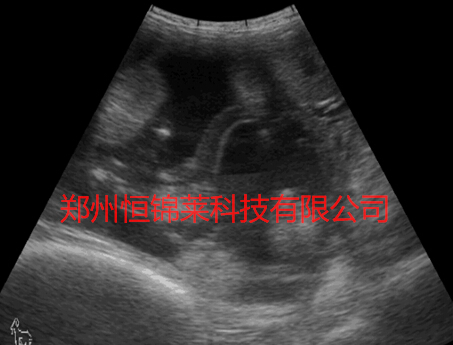

便携式兽用B超检测母羊妊娠

(3)便携式兽用B超检测母羊卵巢囊肿。分为卵泡囊肿和黄体囊肿。卵泡囊肿是卵泡上皮变性,卵泡壁结缔组织增生变厚,卵细胞死亡,卵泡液未被吸收,反而增多,引起囊肿,造成慕雄狂。其症状为母畜频频发情,外阴部下垂,充血,卧地时外阴门张开,伴随流出透明的分泌物,性情粗野,严重时叫声变粗好似公羊声,频频爬跨,频频排尿,尾部出现凹陷,每次发情期6~8天,直肠检查时患侧卵巢肿大,卵泡皮厚富有弹性,摸到实质部,有卵泡液波动。黄体囊肿是由于未经排卵的卵泡壁上皮黄体形成的囊肿。其症状为完全停止发情,卵巢上黄体块突出,且富有弹性。